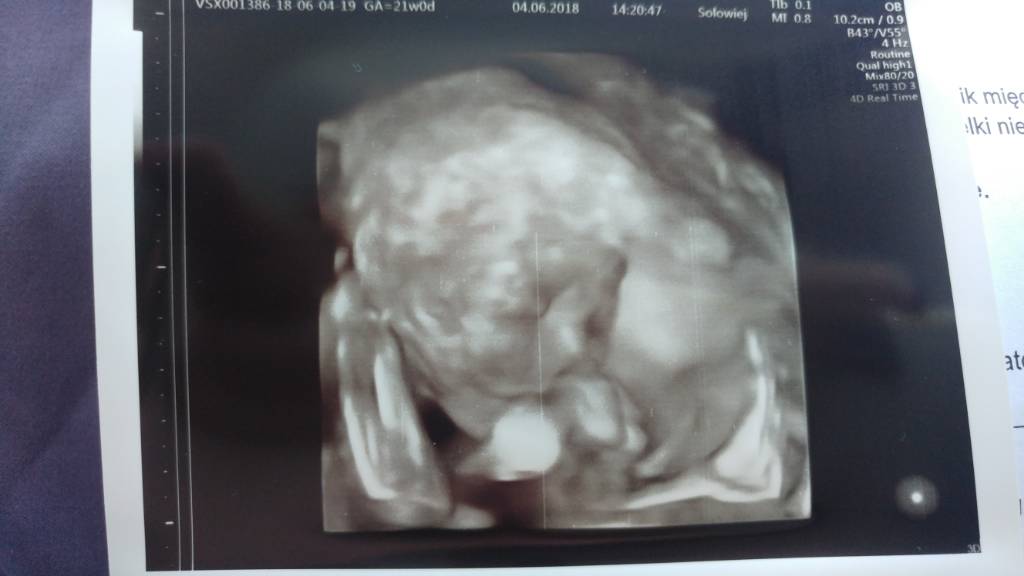

Hej dziewczyny. Ja po połówkowym. Wszystko super. Dziecko według om 21,0 według usg 21,6. Waga 440, dlugi 20 cm. Syn - ale to wiem od 12 tc

Łożysko na scianie przedniej. Szyjka 33 mm. I to jest bardzo dobrze.